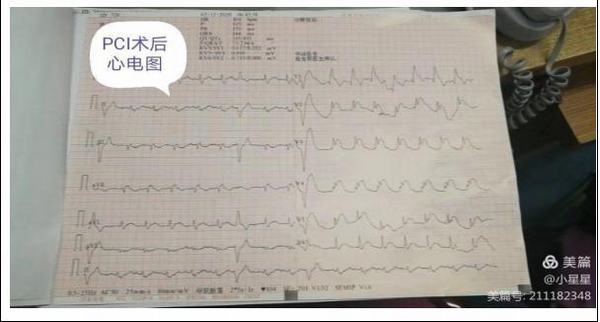

15分鐘后,患者王先生在家屬的陪同下來到了延安大學咸陽醫院心血管病院11樓心六科,在吳醫生問診及查體時患者胸痛再次發作,并于4點20分突然出現四肢抽搐、呼之不應,觸摸頸動脈搏動消失,呼吸呈嘆息樣,立即予以心肺復蘇術,心電監測提示心室停搏,與此同時我科楊登魁責任總醫師、我院心一科王銀濤醫師、心二科代雪茹醫師、心三科王巖醫師、留夜護士陳娜、心七科徐云鵬醫師、留夜護士高謙聞訊趕來,并立即投入緊張的搶救過程中,經予持續胸外按壓、多次電除顫等治療后患者于4點40分意識逐漸恢復,心電監測示加速性室性自主心律,搶救成功,而早己就位的導管室同仁也做好了準備工作,并于6點40分成功開通了患者閉塞血管,術后患者生命體征平穩。